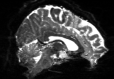

Reversed Gradient Polarity (RGP) methods are commonly used to correct susceptibility artifacts in Echo-Planar Imaging (EPI) [Stehling et al., 1991]. RGP methods acquire a pair of images with opposite phase encoding directions, which leads to a minimal increase in scan time due to the speed of EPI. In a post-processing step, RGP approaches use the fact that the distortion in both images has an equal magnitude but acts in opposite directions to estimate the field map (see Figure 1) [Chang and Fitzpatrick, 1992, Bowtell et al., 1994]. The field map is then used to estimate a distortion-free image.

Refer to captionRefer to captioninput images+v𝑣+vv𝑣-vRefer to captionoptimizeRefer to captionfield map b𝑏bRefer to captionapply modelRefer to captioncorrected image \mathcal{I}

Figure 1: The Reverse Gradient Polarity correction paradigm. Two images are acquired with opposite phase encoding directions, +v𝑣+v and v𝑣-v. These two images are used to estimate the field map b𝑏b, and the distortion correction model [Chang and Fitzpatrick, 1992] is applied to obtain a corrected image \mathcal{I}.